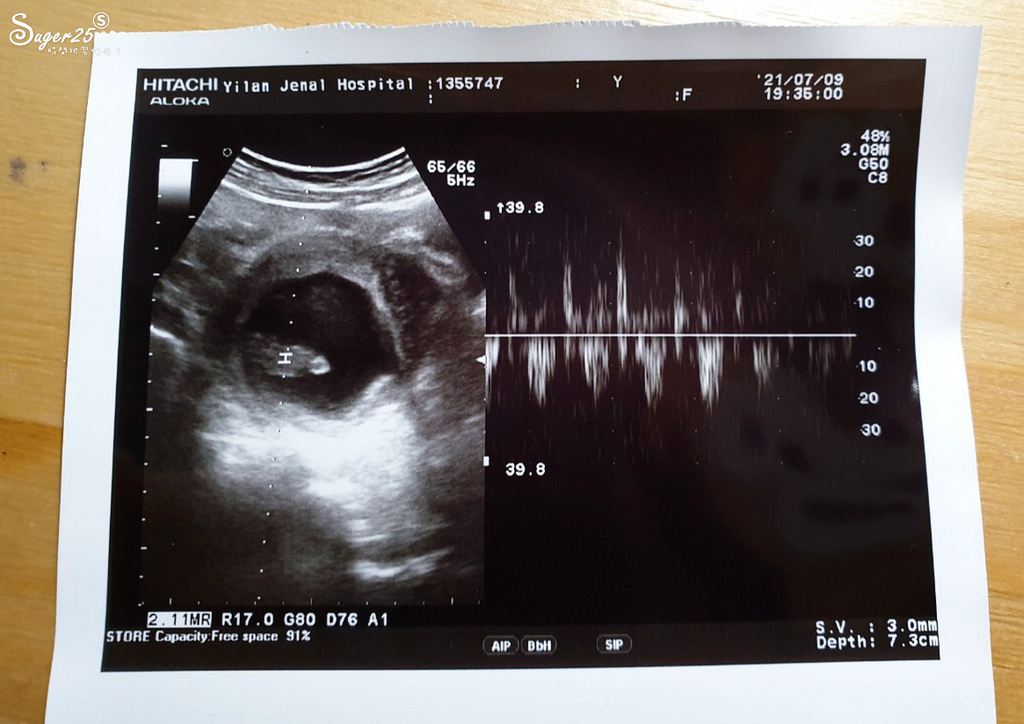

七週產檢時,看到小小顆的心跳但不明顯

八週 很有力的心跳來了!!!

醫生給我媽媽手冊,有小心跳莫名的感動

感覺自己又過了一關卡 呼~